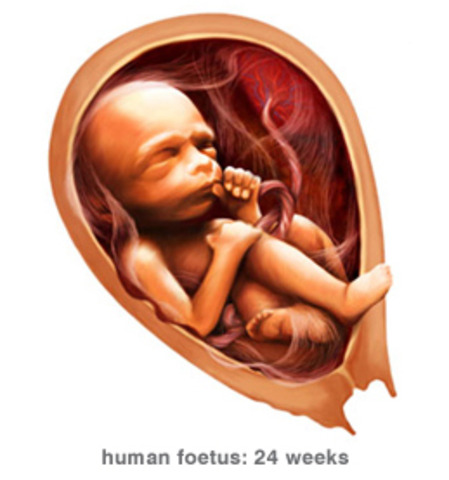

• Week 24

Week 24

Your baby's growing steadily, having gained about 4 ounces His body is filling out proportionally and he'll soon start to plump up. His brain is also growing quickly now, and his taste buds are continuing to develop. His lungs are developing "branches" of the respiratory "tree" as well as cells that produce surfactant. http://www.babycenter.com/6_your-pregnancy-24-weeks_1113.bc